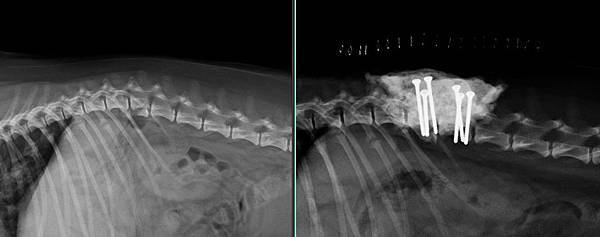

脊椎骨折---加班的深夜手術

可憐的喜樂蒂多多

第一腰椎骨折癱瘓

這是屬於要立刻緊急手術的病況